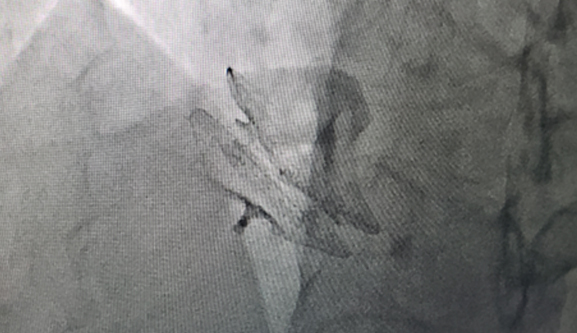

• Post-deployment flouroscopy image of VSO